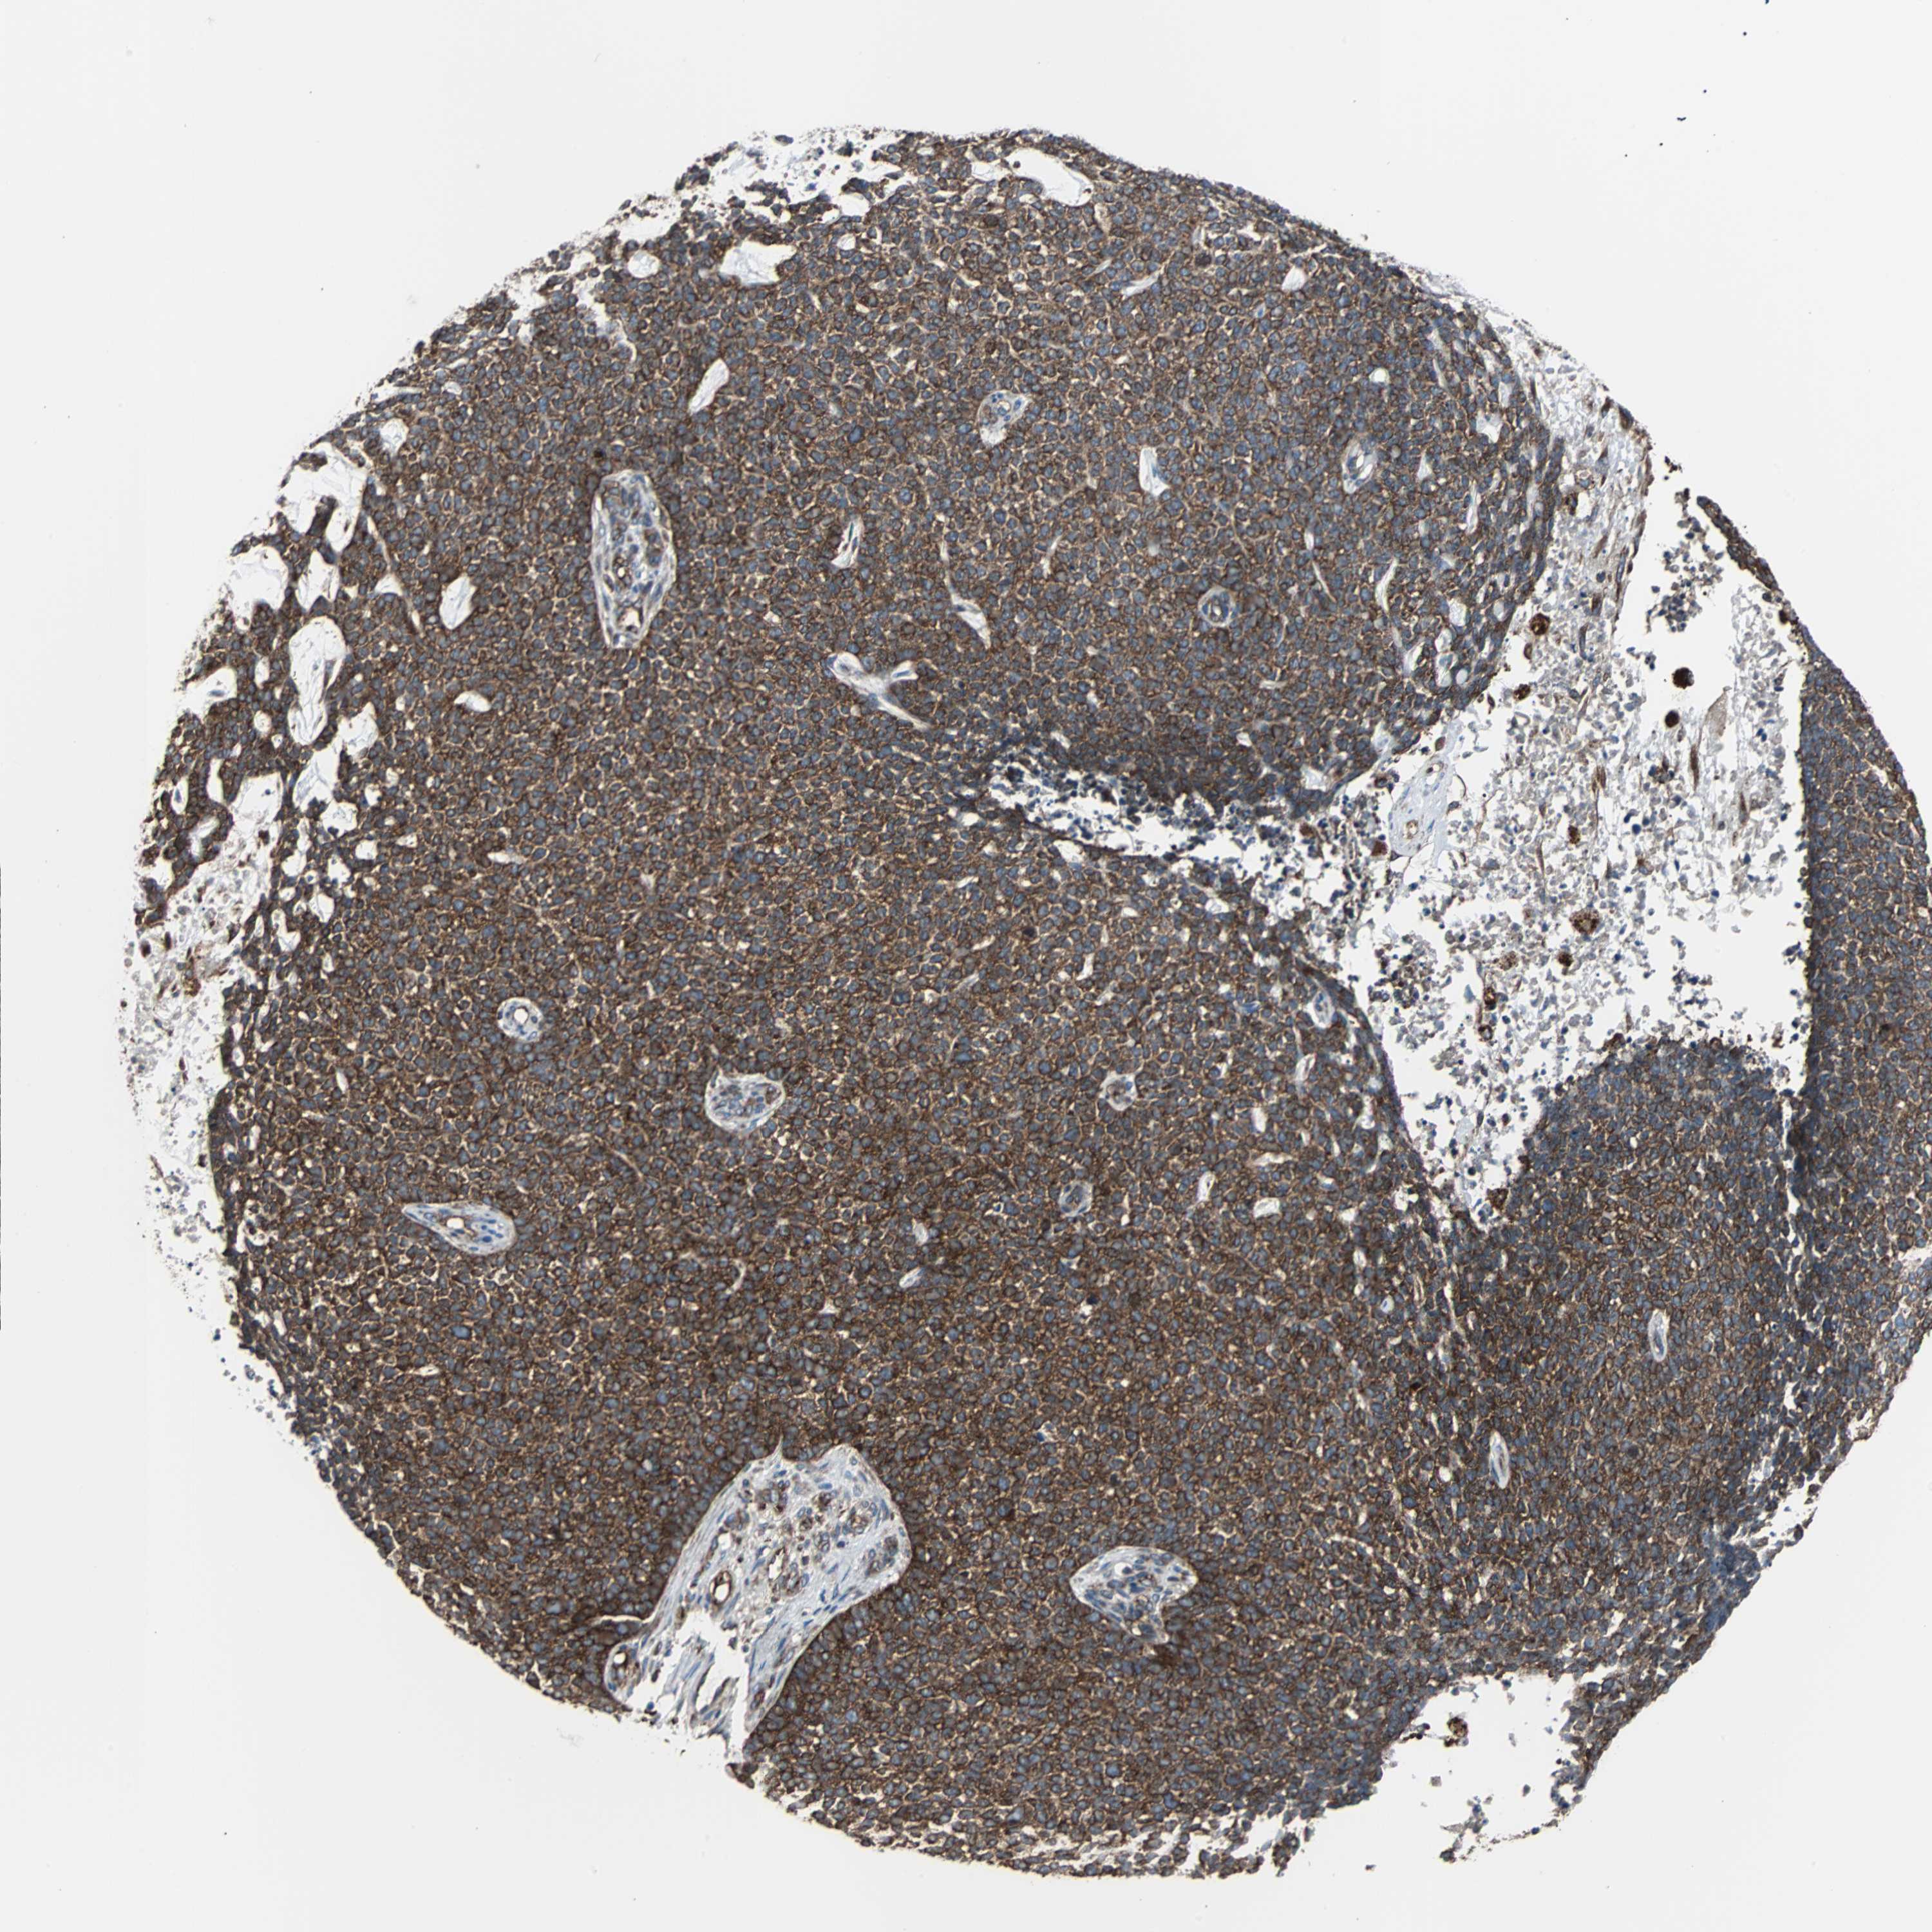

CANCER SKIN CANCER Show tissue menu

Basal cell and squamous cell cancer

SKIN CANCER - Protein expressioni

A mouse-over function shows sample information and annotation data. Click on an image to view it in a full screen mode. Samples can be filtered based on level of antibody staining by selecting one or several of the following categories: high, medium, low and not detected. The assay and annotation is described here.

Each image is clickable and will lead to virtual microscopy that enables deeper exploration of all samples and also displays staining intensity scores, fraction scores and subcellular localization as well as patient and tissue information for each sample.

Antibody CAB004264

Squamous cell carcinoma, NOS

Basal cell carcinoma